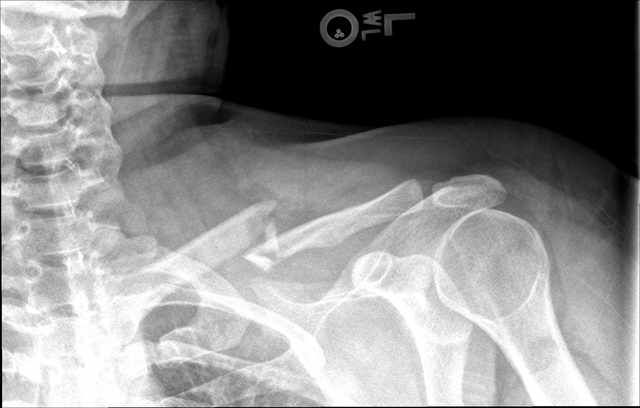

Car Accident

I was in a severe car accident where a car hit my stationary car at 45 miles per hour. My clavical fractured and I had to have surgery.